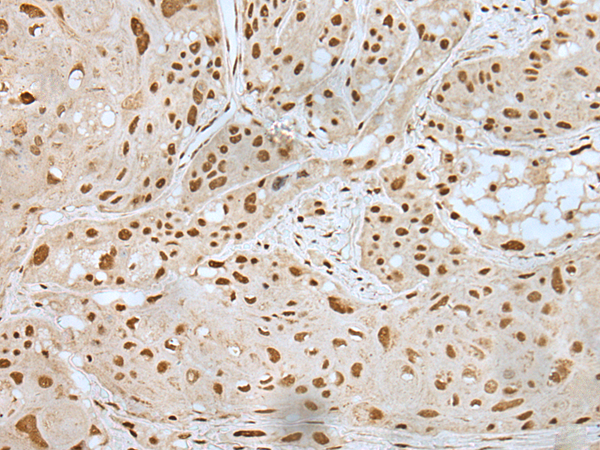

IHC positive control: |

Human esophagus cancer and human liver cancer |